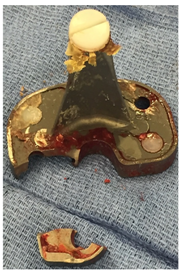

She was taken to the operating room the following day. Her polyethylene was found in the suprapatellar pouch with damage particularly to the posterior medial region (Figure 6). The tibia tray was found to be well fixed but was found to be fractured in the posterior medial corner (Figure 7). Both component revision was undertaken using Zimmer® NexGen® RH knee with cemented stems as well as a trabecular metal femoral cone in the metaphysis (Figure 8).

Figure 6 intraoperative photographs after arthrotomy where the polyethylene was encountered within the suprapatellar pouch. Severe posterior damage to the polyethylene was noted.

Figure 7 Intraoperative photograph showing fracture of the posterior medial corner of the tibial tray, medially, through a hole which allows for optional augment attachment and into the PCL recess of the tray.